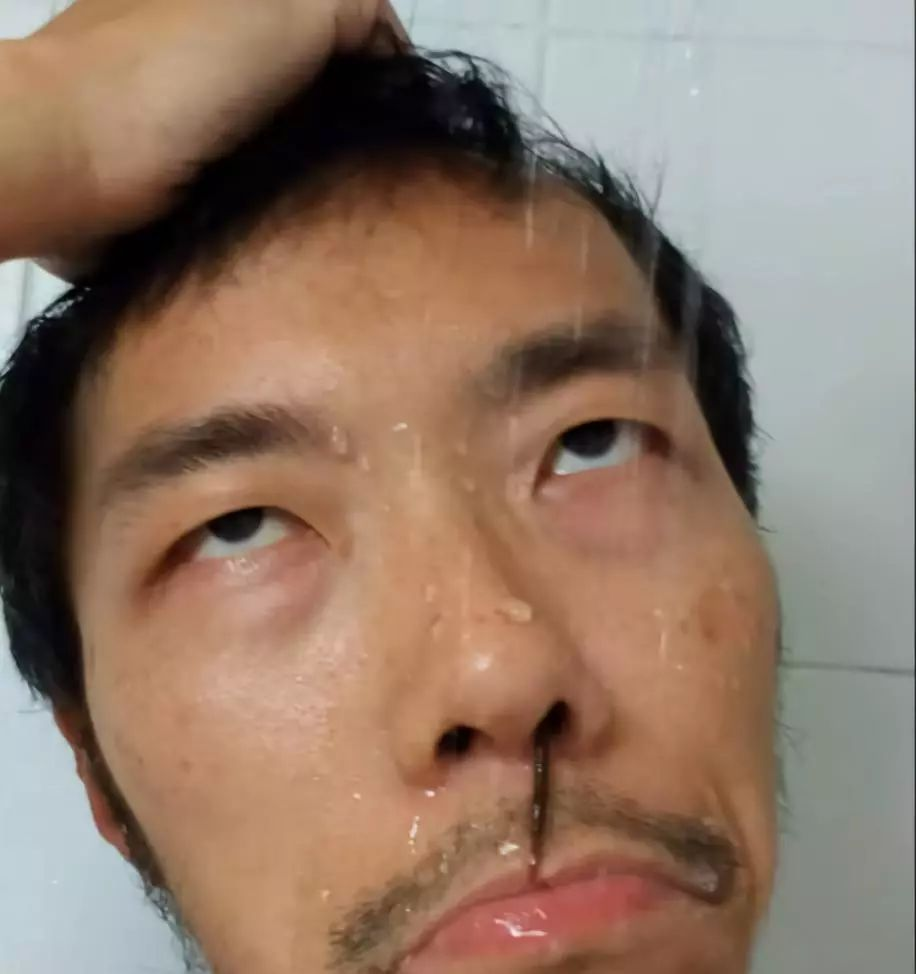

等第25天,他洗澡时能明确感觉到鼻蛭往前探进鼻前庭,并隐约感觉鼻孔内侧出现了异物。之后,鼻蛭便会时不时在洗脸、洗澡等有水的环境时探出头来。

不只是湿度高,周围光线的变化也可能引发鼻蛭探头。比如当他从太阳下走进室内,鼻蛭就可能会探头;又比如每天晚上关灯睡觉时,鼻蛭就会探出来,使他难以安然入睡。就连在电影院里面灯一关,鼻蛭也会探出来一同欣赏电影。让他哭笑不得。所幸鼻蛭探出头的时候都处于黑暗的环境,不至于吓到别人。

洗澡时探出头的鼻蛭,实验者本人